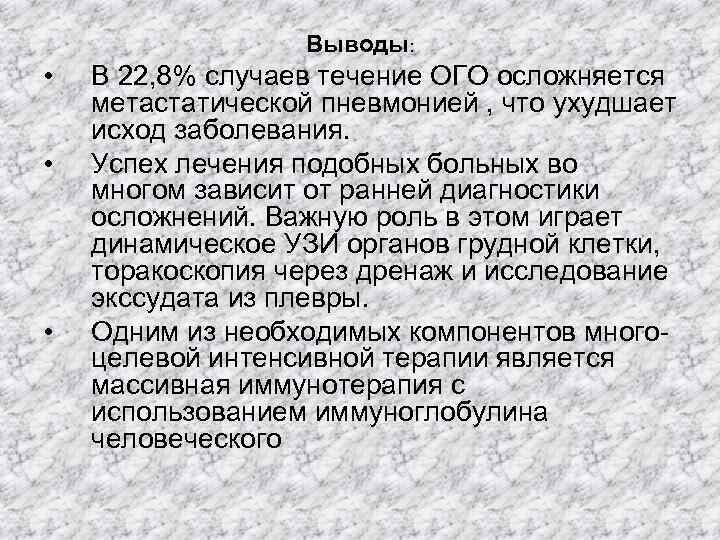

Выводы: • • • В 22, 8% случаев течение ОГО осложняется метастатической пневмонией , что ухудшает исход заболевания. Успех лечения подобных больных во многом зависит от ранней диагностики осложнений. Важную роль в этом играет динамическое УЗИ органов грудной клетки, торакоскопия через дренаж и исследование экссудата из плевры. Одним из необходимых компонентов многоцелевой интенсивной терапии является массивная иммунотерапия с использованием иммуноглобулина человеческого

Выводы: • • • В 22, 8% случаев течение ОГО осложняется метастатической пневмонией , что ухудшает исход заболевания. Успех лечения подобных больных во многом зависит от ранней диагностики осложнений. Важную роль в этом играет динамическое УЗИ органов грудной клетки, торакоскопия через дренаж и исследование экссудата из плевры. Одним из необходимых компонентов многоцелевой интенсивной терапии является массивная иммунотерапия с использованием иммуноглобулина человеческого